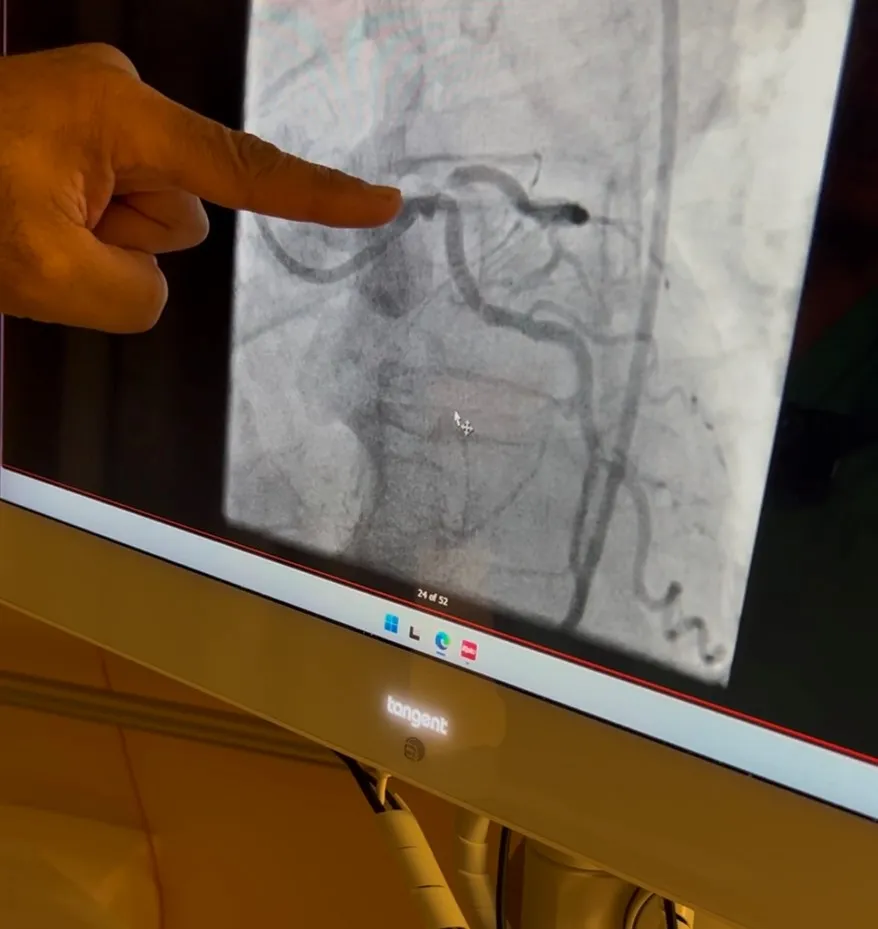

There, doctors discovered a 90% blockage in the vessels at the back of his heart.

“This was as serious as it gets,” recalled Dr. Utpal Desai, a cardiothoracic surgeon at AdventHealth Daytona Beach. “He was getting about 10% of the blood flow to his heart that he needed. So, this was very, very serious. I was concerned his heart might stop again, so we put him on life support and then performed the emergency bypass surgery and his heart came back.”